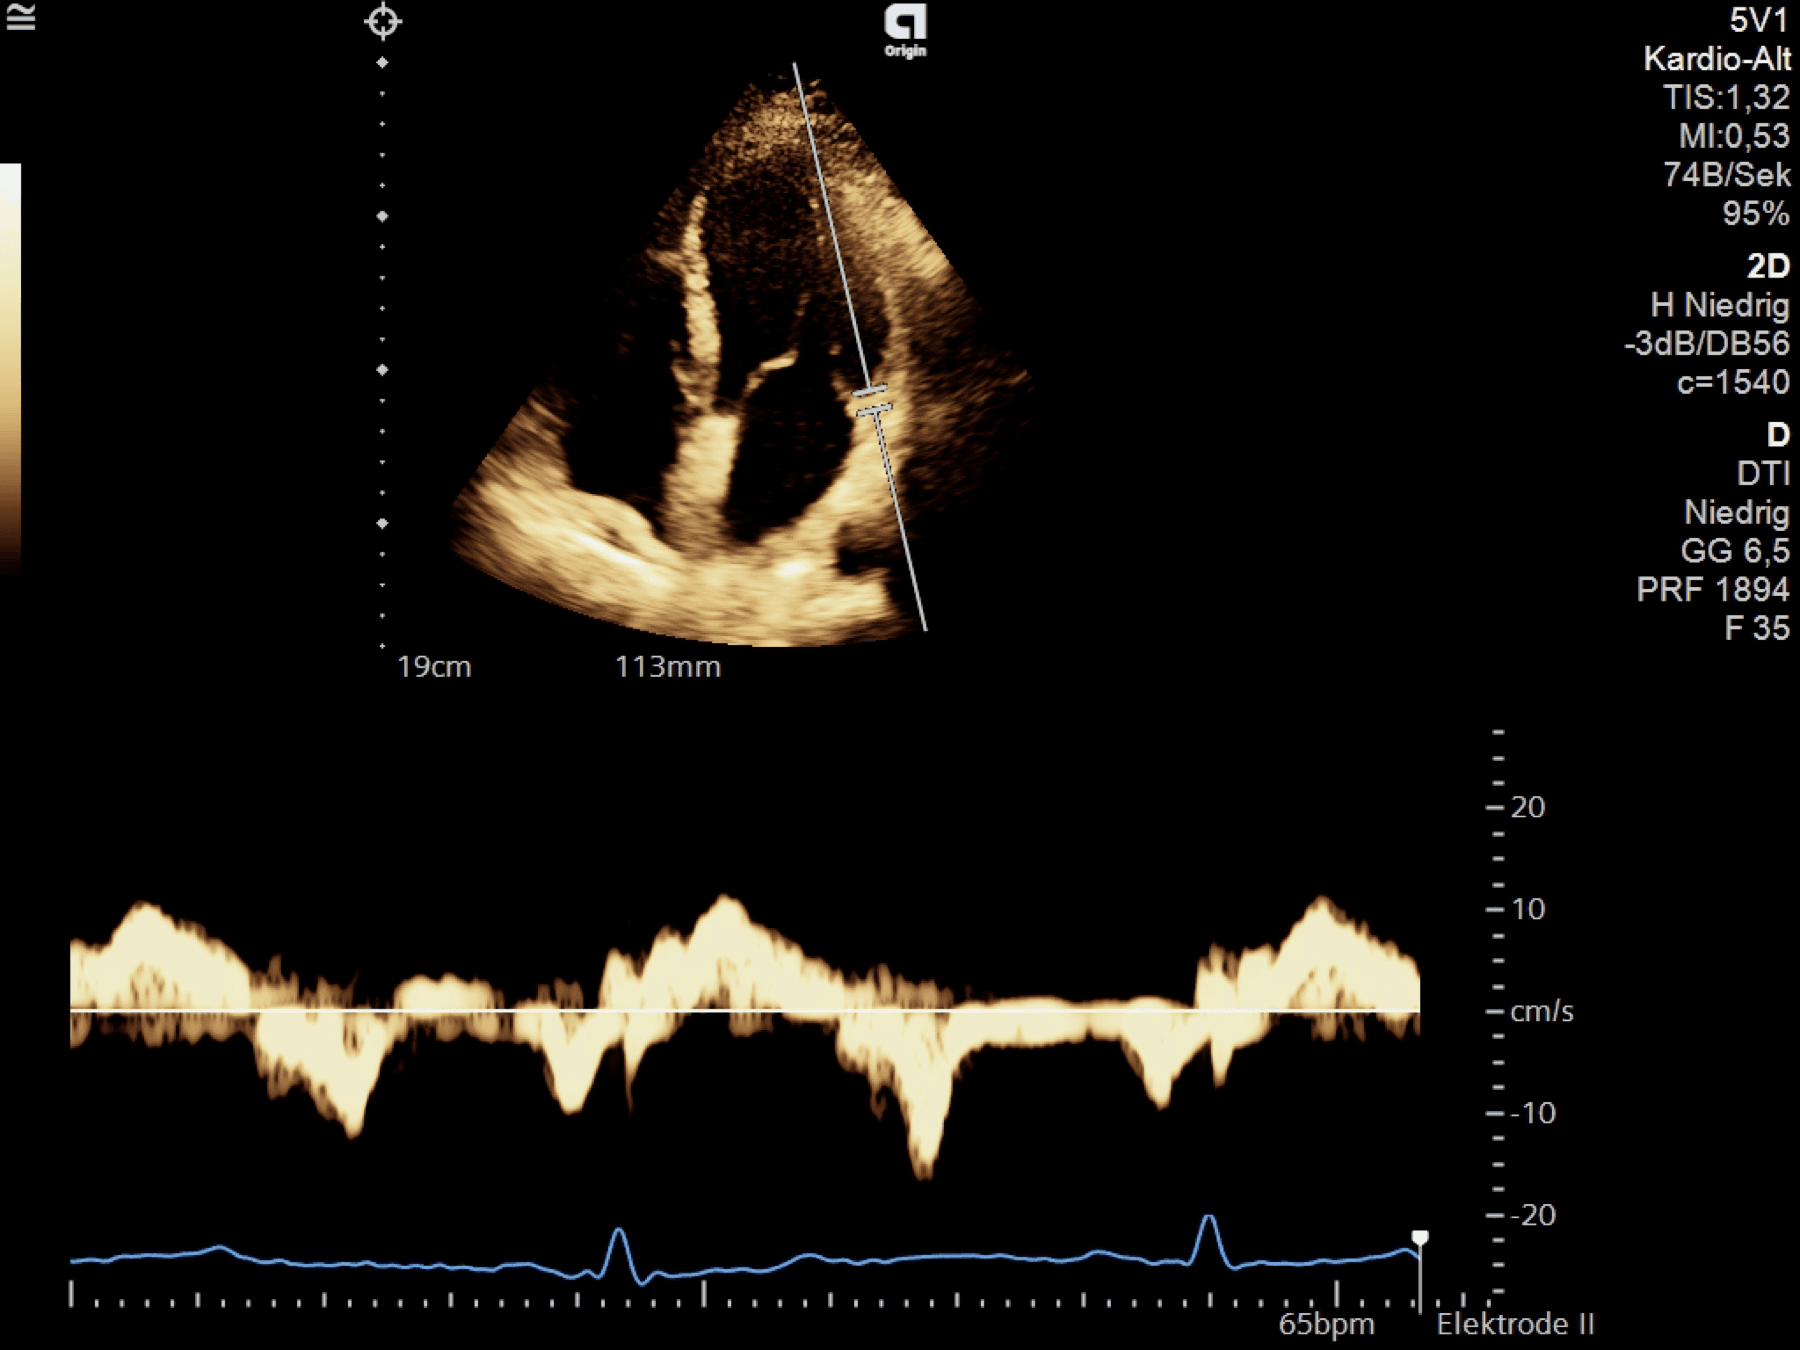

LV systole

IVCT

Mitral valve closure (MVC) to aortic valve opening (AVO)

Isovolumic contraction — LA contraction is finished, LA/LV pressures are almost equal, the MV closes. The LV pressure rises above the LAP, the MV is closed; the pressure is not yet high enough for AV opening ➜ isovolumic contraction phase (part of systole but no output)